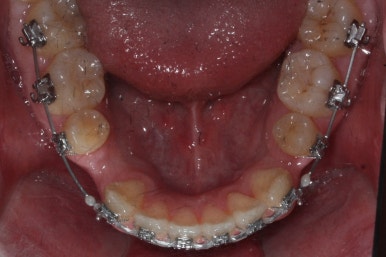

가장 최근의 사진입니다.

아직 치료 종료는 안되었으나 약간의 조절을 더하면 치료를 마무리할 수 있을 것 같습니다.

물론 윗니 한 쪽은 작은 앞니가 없고 한 쪽은 작은 어금니가 없기 때문에 중앙선이 100% 일치하지는 못하겠지만 기능적으로나 미적으로나 매우 개선되었음은 틀림없습니다.

치료 전과 가장 최근의 사진을 비교해 보겠습니다.

좌측이 부산구순구개열 전, 우측이 가장 최근의 사진들입니다.

거꾸로 물리던 앞니가 개선되었습니다.

좁아져 있고 찌그러진 위턱뼈의 형태가 개선되었습니다.

영구치 개수가 모자라는 선천결손이 있었지만 아랫니도 개수를 맞춰줌으로써 치아의 맞물림도 상당히 좋아졌습니다.